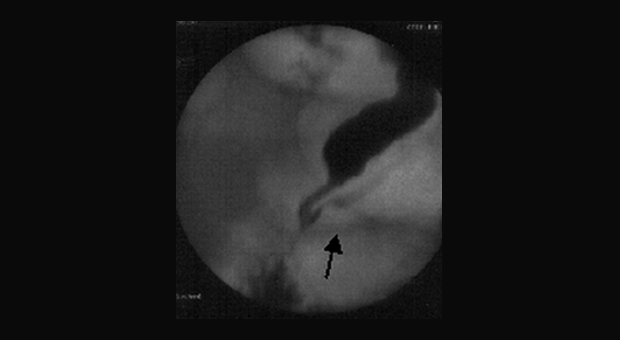

Иллюстрация №2: Выявленный на РХПГ билиарно-панкреатический рефлюкс

Выявленный на РХПГ билиарно-панкреатический рефлюкс так же позволяет заподозрит эту патологию, особенно при наличии у пациента клиники идиопатического рецидивирующего панкреатита. Картина рефлюкса представлена на следующем рисунке.